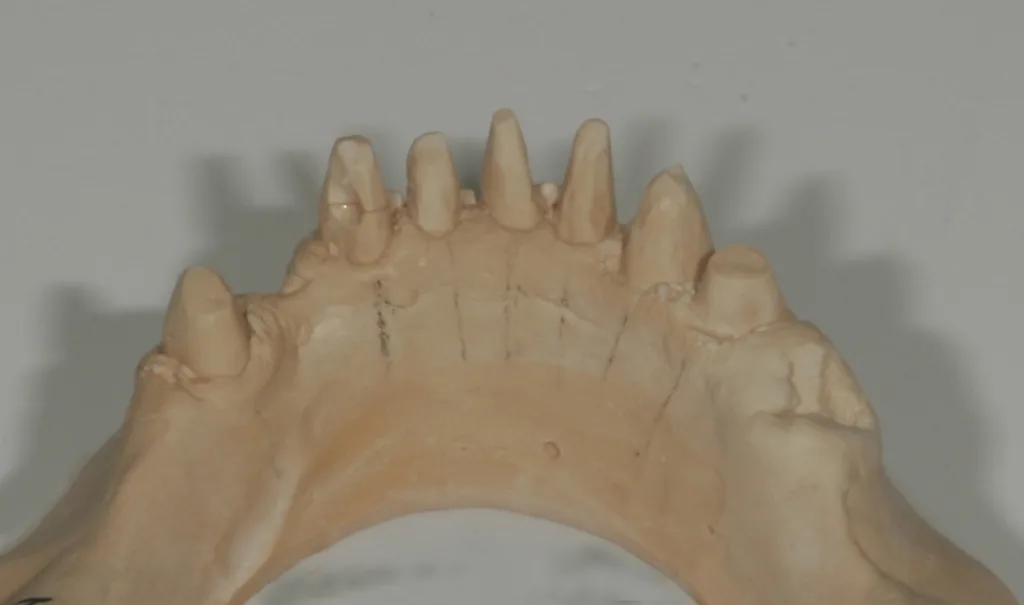

Eine noch verhältnismäßig jung wirkende 76-jährige Patientin musste im Unterkiefer neu versorgt werden, da die alte VMK-Brückenkonstruktion wegen Pfeilerverlusts komplett entfernt werden sollte. Seit mehr als 10 Jahren bestand bereits eine Teleskopversorgung im Oberkiefer – nunmehr war auch für den Unterkiefer eine solche vorgesehen. Ein besonderes Anliegen war der Patientin eine brückenartige Konstruktion, d.h. ohne Sublingualbügel. Bei der Farbgestaltung war der Wunsch, dass sie eine Nuance heller sein sollte als die Zähne im Oberkiefer, und keinesfalls sollten die Zähne einen gelblichen Stich bekommen. Beim Situationsmodell von bukkal zeigte sich, dass schon früher der Zahn 33 unter der Brücke entfernt worden war (Abb. 1) und der Knochen in diesem Bereich stark atrophiert war. In der Ansicht von lingual (Abb. 2) sind der „Zahnstummel“ 44 und die Extraktionswunde 45 gut ersichtlich.

Nachdem die Abformungen desinfiziert und auf Fehlstellen hin untersucht worden waren, erfolgte das Ausgießen und nach dem Aushärten das Entformen (Abb. 6). Der „Zahnstummel“ 44 war zwischenzeitlich aufgebaut worden und hatte nun eine ideale Präparationsform. Um die filigranen Stümpfe im Frontbereich nicht noch mehr zu schwächen – später werden diese beim Kauen durch die Hebelbelastung der Freiendsättel deutlich belastet –wurde nur so weit nachpräpariert, wie es unbedingt notwendig war. Anschließend war das Modell von basal und vestibulär zu trimmen. Die Lingualfläche ließ sich sehr gut mit einem SGFA-Fräser (Komet) bearbeiten.